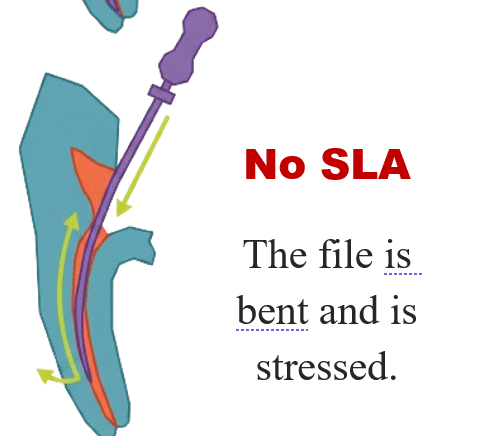

- Cyclic fatigue — repeated flexing in curved canals leading to fracture.

- Torsional stress — when file tip locks but shaft keeps rotating.

Pre-operative prevention

- Study preoperative radiographs or CBCT.

- Achieve straight-line access.

Step 1 — Improve access

Create straight-line access